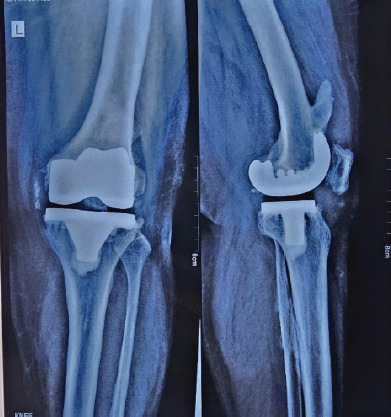

Case report: We report the case of a 67-year-old female with grade 4 osteoarthritis of the left knee who underwent TKR following the failure of conservative management. Postoperatively, the patient developed stiffness and a reduced range of motion. Radiographic imaging at 5 weeks showed haziness in the anterior aspect of the femur at the upper border of the femoral implant, with gradual progression to distinct ossification by 3 months.

Results: The heterotopic bone formation was found to impinge on the quadriceps mechanism, limiting knee flexion but not preventing full extension. Conservative management involving physiotherapy and analgesics was pursued, and surgical excision was avoided initially. Over 1 year, the patient showed improvement in extension, although no significant improvement in flexion was observed. Surgical excision of the heterotopic bone was performed at the end of 1 year, followed by post-operative radiotherapy to prevent recurrence.